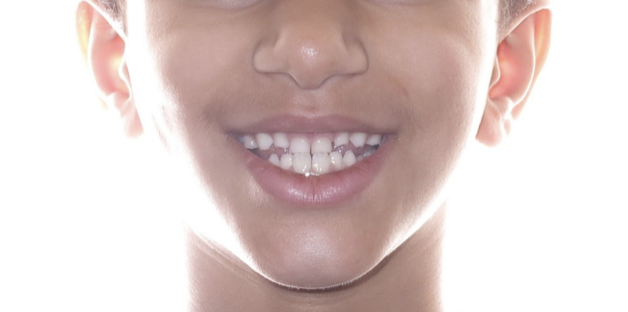

Underbite Before and After

Before